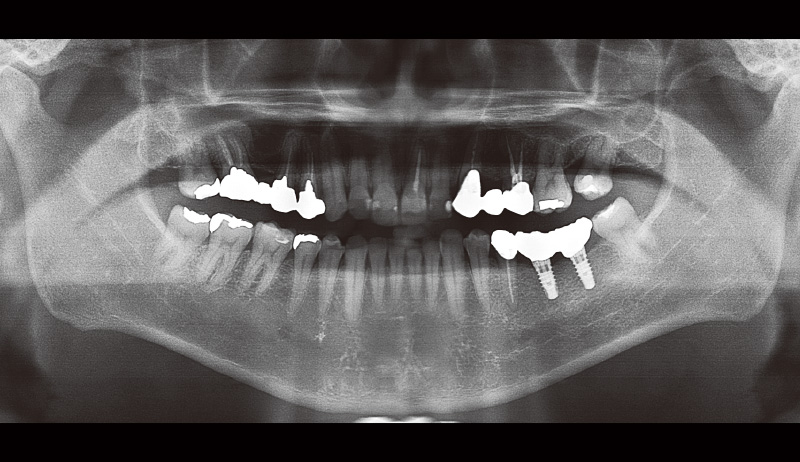

主訴:左下の奥歯で噛めるようになりたい(図6, 7)。

₆、₇にインプラントを埋入し左側の咬合を得る治療計画を立案。φ4.5長さ9.5mmのSPIイニセルインプラント エレメントRCを埋入した(図8)。まずはここで初期固定を得られたのでヒーリングキャップにて封鎖した(図9)。今回は勤務医たちへの指導の意味もあり、ガイデッドサージェリーにて行った。そして4週目でクローズドトレーにてシリコン印象を行い補綴装置をセットした(図10,11)。CBCT撮影を行い骨レベルの状態を確認し、機能的審美的にも問題ないことがわかっている(図12, 13)。

![[写真] 初診時のパノラマX線写真(2024年9月12日)](/academic/dentalmagazine/wp-content/uploads/sites/2/2025/09/194-8_photo07.jpg)

図7 初診時のパノラマX線写真(2024年9月12日) -

![[写真] インプラント埋入後のパノラマX線写真(2024年9月28日)](/academic/dentalmagazine/wp-content/uploads/sites/2/2025/09/194-8_photo08.jpg)

図8 インプラント埋入後のパノラマX線写真(2024年9月28日) -